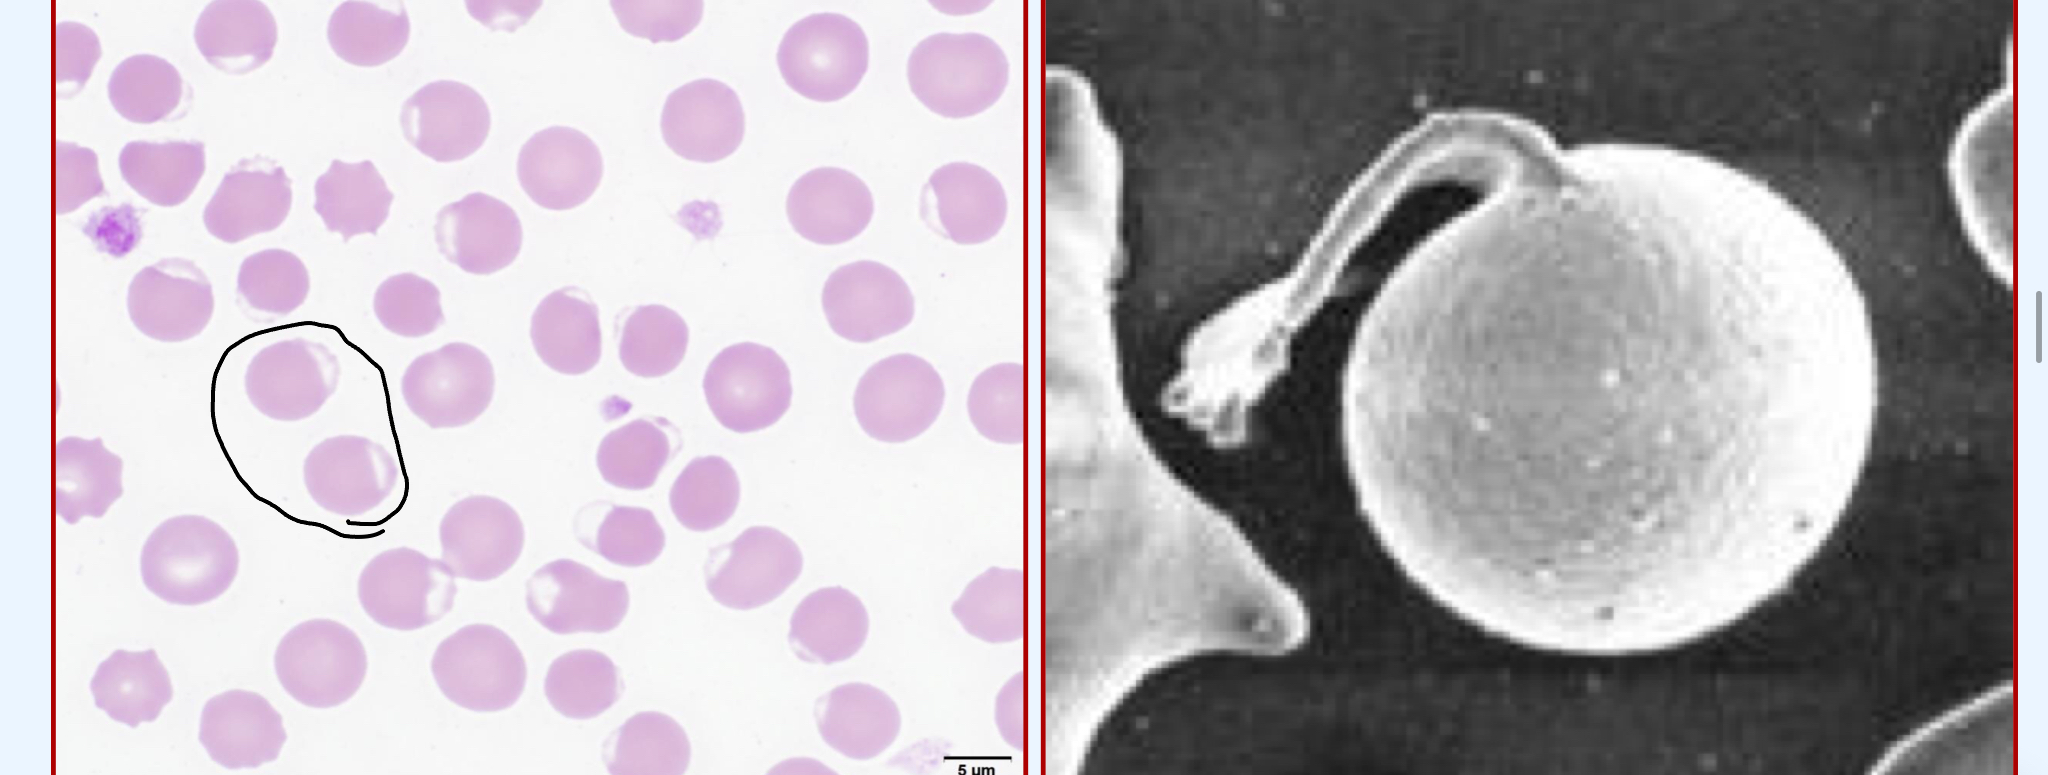

Spherocyte

Lack central pallor (one solid color)

Smaller than RBCs (look similar to microcytes)

What is the clinical significance of finding Spherocytes?

IMHA (very common)

Fragmentation hemolysis

Envenomation

Zinc toxicosis

IMHA is at the top of your differential list when spherocytes are present